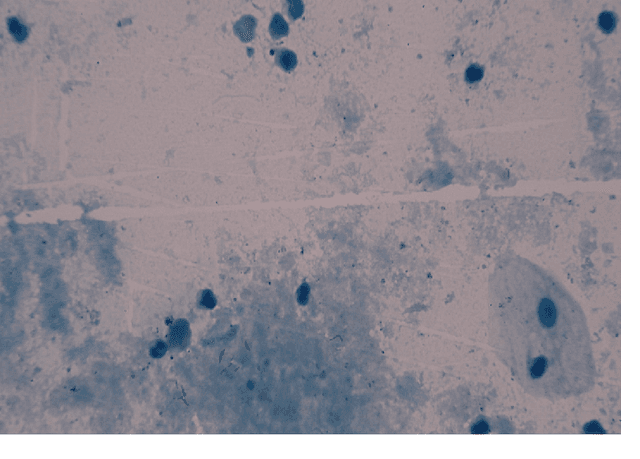

Abstract:Tuberculosis is a contagious disease which is one of the leading causes of death, globally. The general diagnosis methods for tuberculosis include microscopic examination, tuberculin skin test, culture method, enzyme linked immunosorbent assay (ELISA) and electronic nose system. World Health Organization (WHO) recommends standard microscopic examination for early diagnosis of tuberculosis. In microscopy, the technician examines field of views (FOVs) in sputum smear for presence of any TB bacilli and counts the number of TB bacilli per FOV to report the level of severity. This process is time consuming with an increased concentration for an experienced staff to examine a single sputum smear. The examination demands for skilled technicians in high-prevalence countries which may lead to overload, fatigue and diminishes the quality of microscopy. Thus, a computer assisted system is proposed and designed for the detection of tuberculosis bacilli to assist pathologists with increased sensitivity and specificity. The manual efforts in detecting and counting the number of TB bacilli is greatly minimized. The system obtains Ziehl-Neelsen stained microscopic images from conventional microscope at 100x magnification and passes the data to the detection system. Initially the segmentation of TB bacilli was done using RGB thresholding and Sauvola's adaptive thresholding algorithm. To eliminate the non-TB bacilli from coarse level segmentation, shape descriptors like area, perimeter, convex hull, major axis length and eccentricity are used to extract only the TB bacilli features. Finally, the TB bacilli are counted using the generated bounding boxes to report the level of severity.